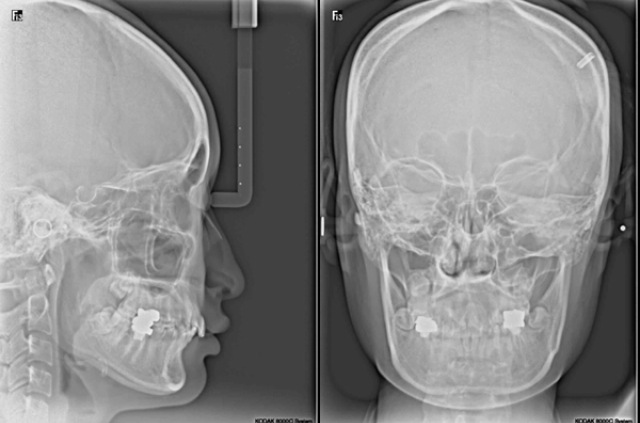

image.jpeg

image-3.jpeg

조금 더 갸름한 정면을 원합니다

귀뒤로 사각,근육 피질 세가지 동시에 하시면 되는데요. 피질은 크지 않으므로 서비스로 해드리겠습니다.

님의 경우 귀뒤로 뼈와 근육을 동시에 수술 받으시면 정면, 측면 모두 만족하시게 됩니다.사각은 사각턱 뼈만 해도 될 경우 길이에 관계없이(돌려 깎기 포함)350입니다.